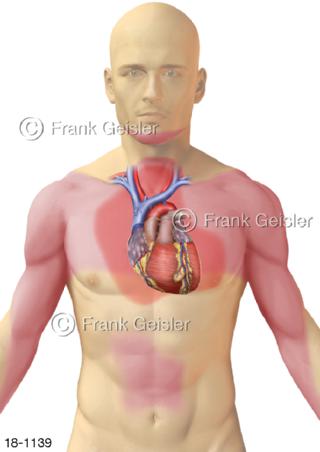

18-1139 Herzerkrankung Brustenge Angina pectoris